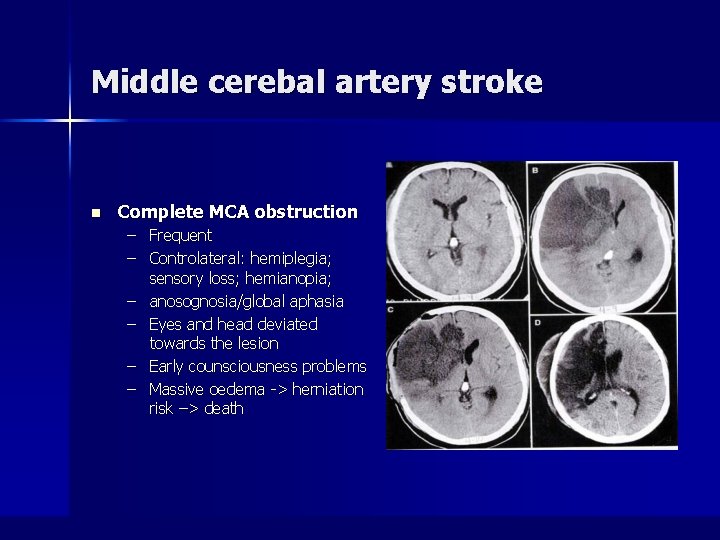

Middle cerebal artery stroke n Complete MCA obstruction – Frequent – Controlateral: hemiplegia; sensory loss; hemianopia; – anosognosia/global aphasia – Eyes and head deviated towards the lesion – Early counsciousness problems – Massive oedema -> herniation risk –> death